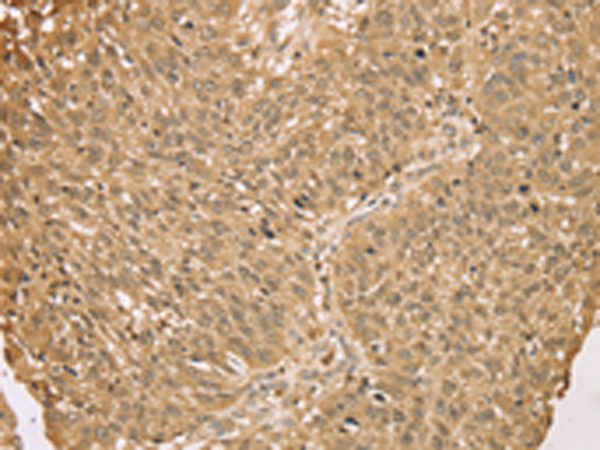

分类: 科研抗体货号: P08748别名: DCE; SELADIN1; Nbla03646; seladin-1应用: WB,IHC反应种属: Human, Mouse, Rat